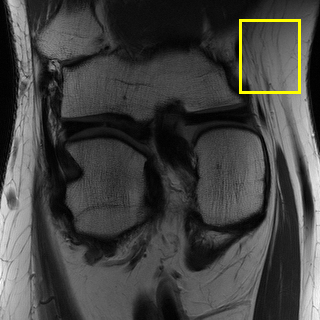

fastMRI is a large-scale MR dataset jointly established by Facebook AI Research and NYU Langone Health. It provides both knee and brain datasets for evaluation. In our work, we use the multi-coil knee dataset, which was acquired on three clinical 3T systems or one clinical 1.5T system using a 15-channel knee coil array. The dataset includes data from two pulse sequences, yielding coronal proton-density weighting with (PDFS) and without (PD) fat suppression. As is shown in Fig. 1, PD images usually contain more structural and prominent edge features than PDFS images, which suggests that it is more challenging to use edge guidance on PDFS datasets. Therefore, we explore the effectiveness of EAMRI on these two modalities. Following [13], for both PD and PDFS knee datasets, we separately filter out 227 volumes (8332 slices) for training and 24 volumes (1665 slices) for testing. The dataset is centrally cropped to .

In Table 2, we provide the quantitative results of all the models over three multi-coil datasets: Calgary [37], fastMRI PD [50], and fastMRI PDFS [50]. According to the table, we clearly observe that EAMRI achieves the best performance over all these datasets under both AF 4 and AF 6. For the T1-weighted images (Calgary) and the PD images (fastMRI PD), whose edge features are more prominent and structural (see Fig. 1), EAMRI can achieve high-performance gain when compared with the second-best model. For example, when the AF = 4, PSNR is boosted by 0.64 over Calgary, and 1.26 over fastMRI PD. On the other hand, for the PDFS images under AF 4, PSNR is boosted by 0.22 when comparing EAMRI with the second-best model. This is because PDFS images usually contain more broken edges, which is more challenging to use the edge guidance mechanism. Fortunately, our EAMRI can still achieve better results, thanks to its well-designed network structure and edge priors.